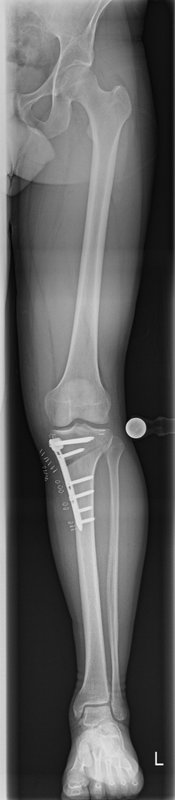

Tibiakopf Fraktur

Die arthroskopisch assistierte Frakturversorgung (insbesondere am Tibiakopf) im Rahmen von Band- bzw. Kombinationsverletzungen ist ebenfalls ein Schwerpunkt der Abteilung. Der ärztliche Direktor PD Dr. med. Schlumberger ist im DKG-Komitee „Frakturen“ vertreten.